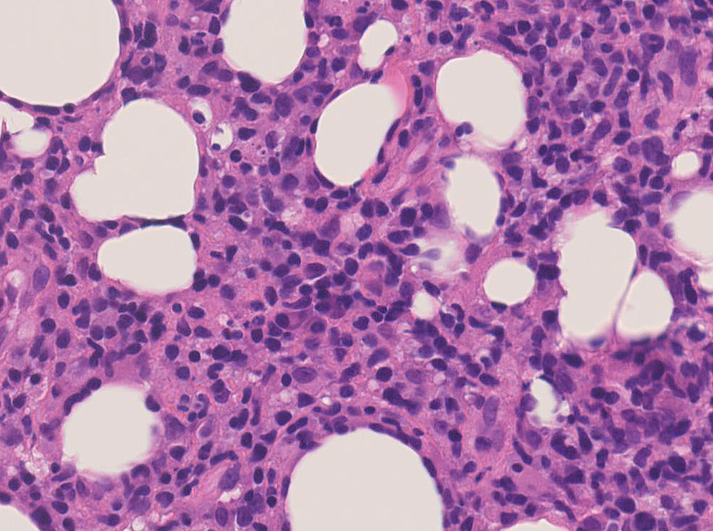

リンパ腫の定義: SPTCLは成熟細胞障害性T細胞(cytotoxic T-cell)由来で、皮下組織に脂肪識炎に似た組織像を呈しながら増殖する悪性リンパ腫。

組織所見*16*17*18

皮下組織に優位な, 小~中型 Tリンパ球の密な浸潤が特徴。ときに大型リンパ球や組織球が混在する。 リンパ球の異型は, わずかなものから明瞭な異型を示す症例までさまざまである。